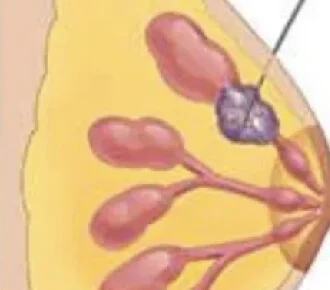

- Biopsias o Resección de Mama